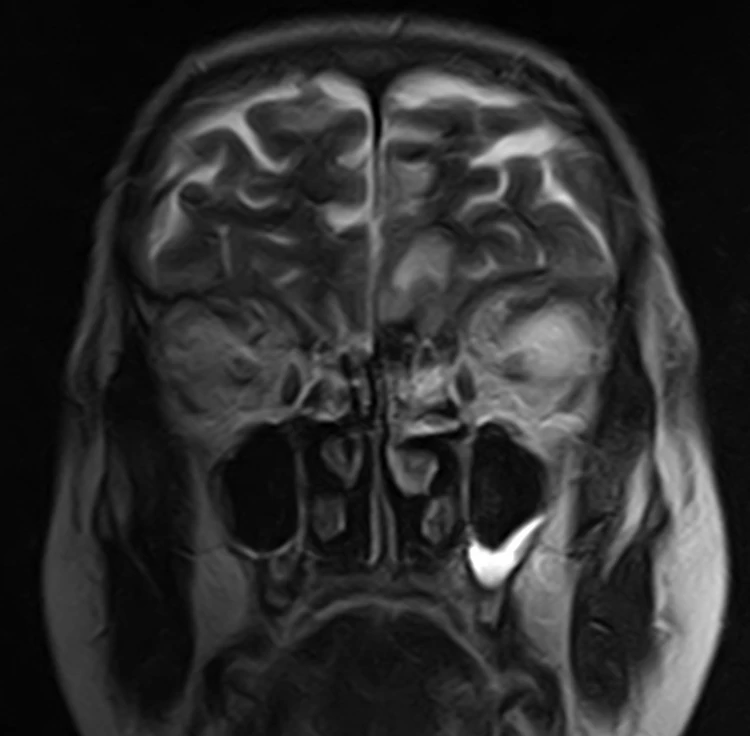

Снеговики бывают разные, но смысл симптома при аденоме гипофиза от этого не меняется: когда опухоль растёт вверх, она протискивается черезу дуральную селлярную диафрагму и в этом месте на ней явственно определяется поясок. Это, как утверждается, достаточно надёжный дифференциально диагностический признак (точность порядка 94-96%) именно аденомы гипофиза, а не какой-то другой опухоли данного расположения.